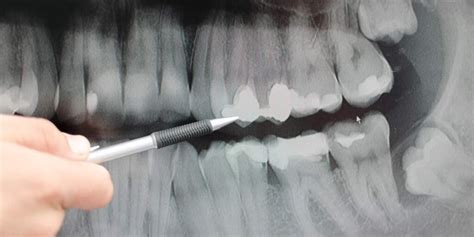

¿Cómo se Detecta el Sarro en una Radiografía Dental?

En las radiografías dentales, el sarro subgingival puede aparecer como pequeñas protuberancias o depósitos irregulares en las raíces de los dientes. Estas imágenes ayudan al dentista a evaluar la extensión del sarro y planificar el tratamiento adecuado.

Además de la radiografía, el dentista puede realizar un examen clínico exhaustivo para detectar la presencia de sarro subgingival y evaluar la salud de las encías.